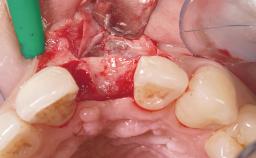

Staged bone augmentation of the alveolar ridge is indicated whenever a proposed implant site is deficient and will not support implant placement with simultaneous grafting. This is particularly true of healed sites presenting with facial flattening of the ridge. Since primary stability cannot possibly be achieved in this situation, it is recommended to use a staged approach with guided bone regeneration (GBR) for correct three-dimensional placement of the implant. In the anterior maxilla, staged GBR procedures are conducted not only to provide adequate bone volume for implant placement but also to restore a proper and stable contour of the orofacial ridge for improved long-term esthetics. A case is presented that demonstrates the technique for single-tooth replacement utilizing a staged approach with a particulate grafting material. A 50-year-old man whose tooth 11 was missing presented for consultation to the Center for Implant Dentistry in January 2010.